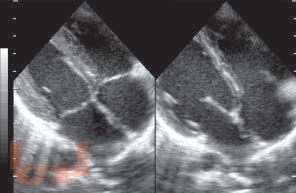

Книга посвящена одному из важнейших разделов детской кардиологии - врожденным порокам сердца. В общей части рассмотрены особенности нормального кровообращения у плода и новорожденного, а также его изменения при врожденной патологии сердца; кроме того, читатель знакомится со специальной терминологией. В разделе частной патологии подробно представлены все основные пороки, встречающиеся в практике детских врачей, алгоритмы их диагностики, современные возможности терапевтического и хирургического лечения; изложены вопросы послеоперационного наблюдения за пациентами. Издание содержит более 140 рисунков и схем, иллюстрирующих ключевые расстройства гемодинамики, методы исследования сердца и наиболее распространенные операции.

Изображения 84